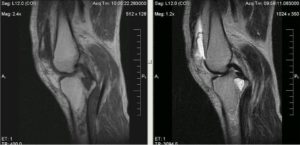

- УЗИ мягких тканей;

- магнитно-резонансную или компьютерную томографию коленного сочленения проводят в том случае, если болезнь рецидивировала не первый раз, либо была вызвана травмированием сустава.